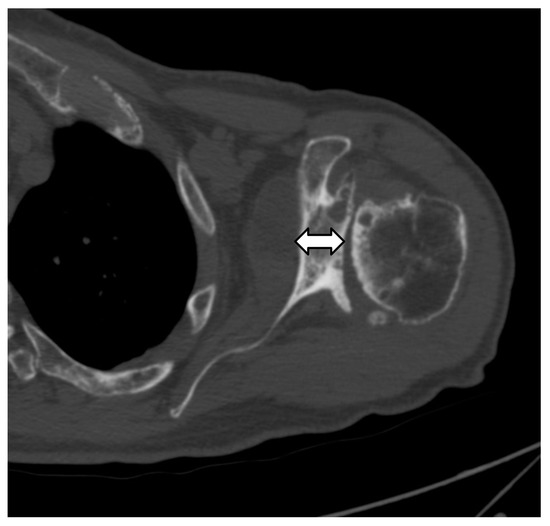

4.2.3. Periprosthetic Joint Infection (PJI)

4.2.4. Rotator Cuff Tendon Tears